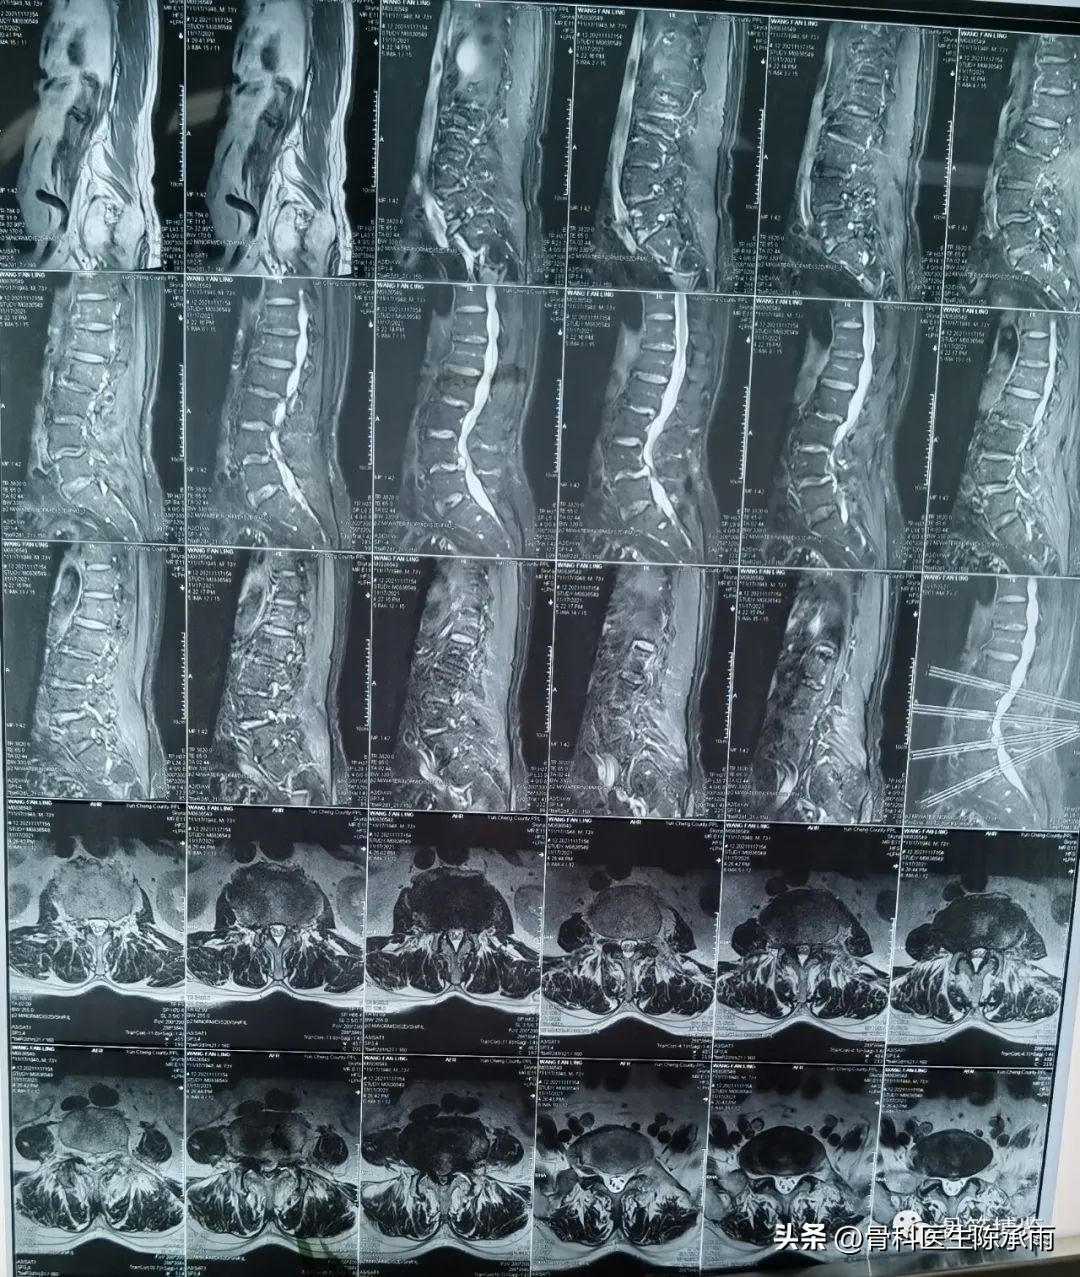

2例 多个间隙狭窄,以腰3/4和4/5为重

术前影像

术中充分减压,由于椎管严重狭窄及黄韧带钙化给手术带来极大困难。还好一切顺利。术中保证了减压彻底,并有效避免了脊髓硬膜及神经根的损伤。